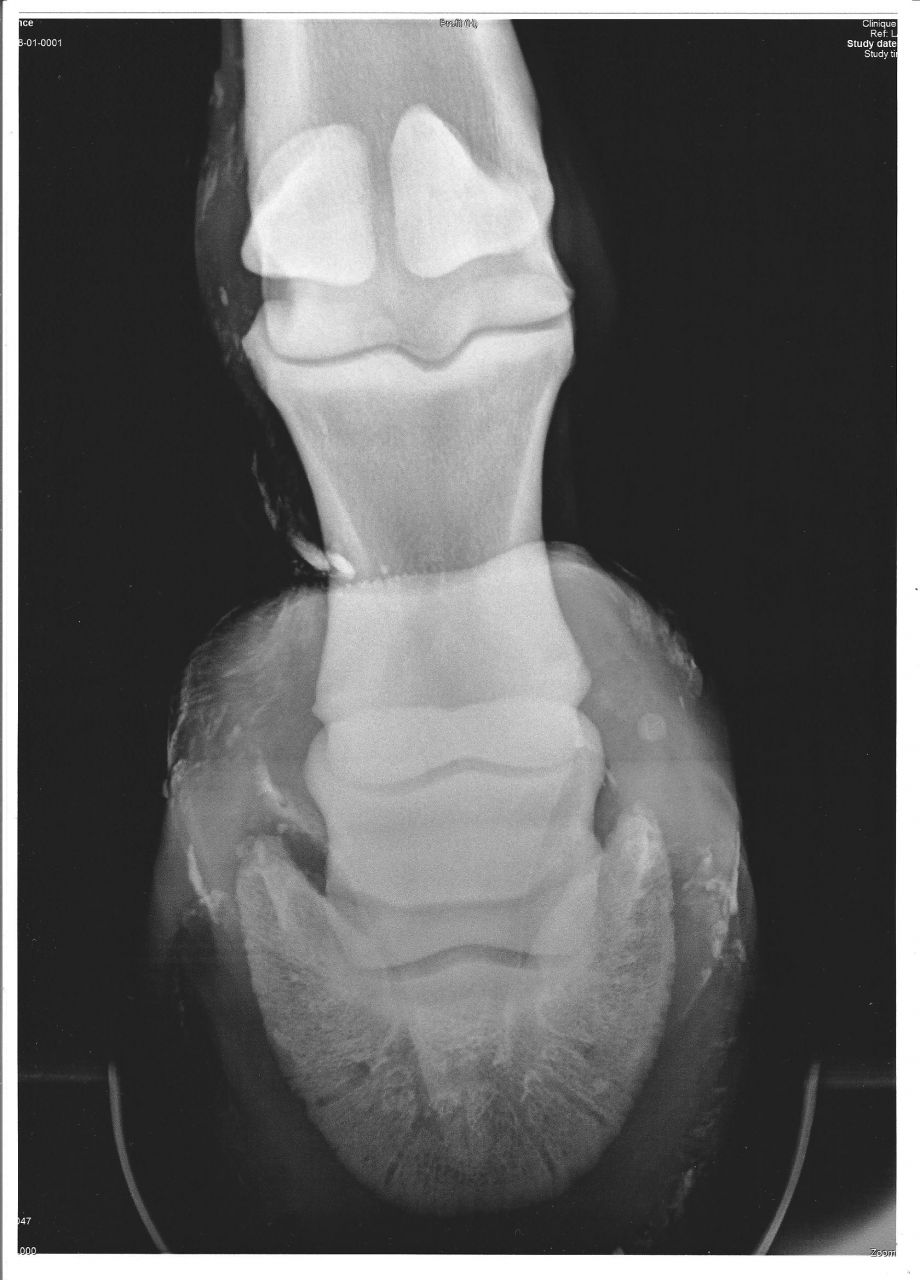

| Dire merci | Mon loulou a eue une fracture du processus palmaire ( os du talon ) qui, d'après mon véto et MF ne se ressoudera pas... Ce n'est pas douloureux et ne fait pas boiter. les conséquences et séquelles à long terme de cette fracture ne sont pas connue car on ne s'en apperçoit pas si on ne fait pas une radio du pied... donc, certains chevaux ont çà, sont montés et vivent normalement, sans que leur proprios le sachent... Mais j'aimerai trouver des articles et/ou témoignages sur tous çà... Quelqu'un saurai ou je pourrais trouver ces infos ? Merci d'avance |

| Dire merci | les radios: La fracture est juste au dessus du vis ( qui n'est pas dans le sabot ) |